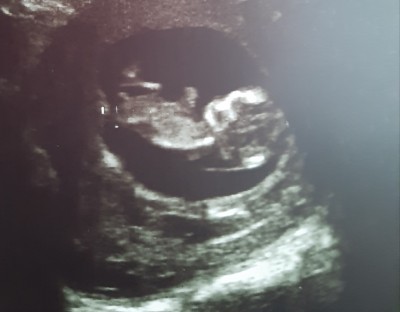

Bak yükledim

image

Bana kordon gibi gelmedi

Bence erkek pipi bursayım dio:))))